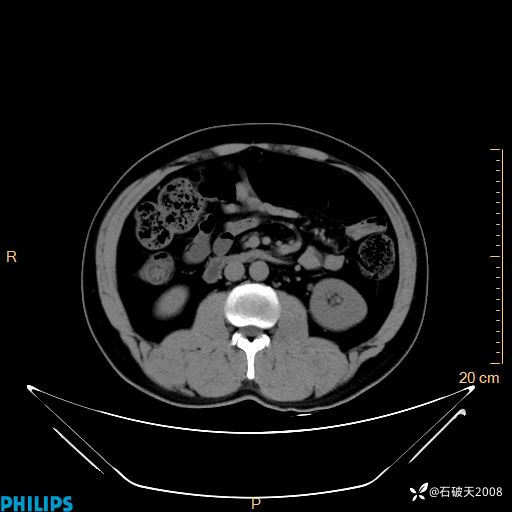

增强轴位